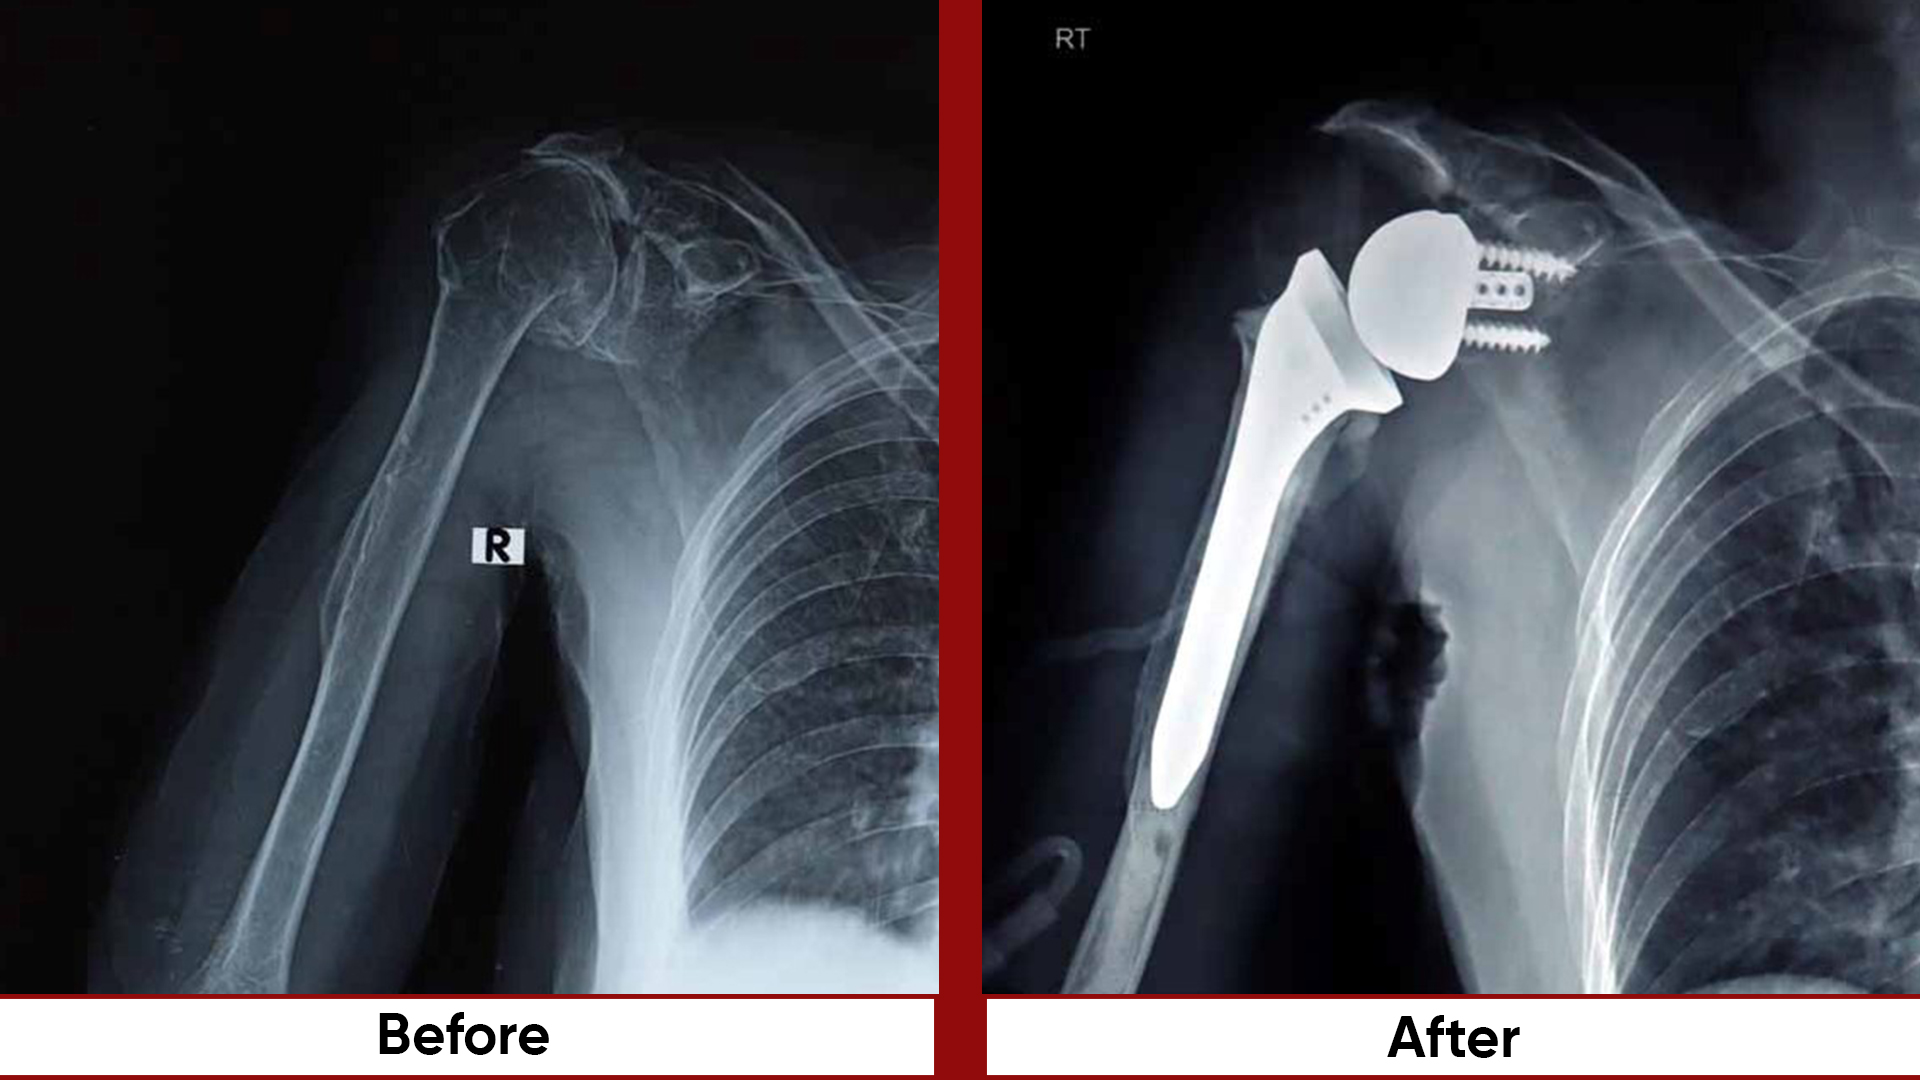

• Total Knee Replacement (TKR)

• Total Hip Replacement (THR)

• Arthroscopic Surgeries (Knee & Shoulder)

• Arthroplasty

•  Arthroscopy / sports injuries.   Busiest unit